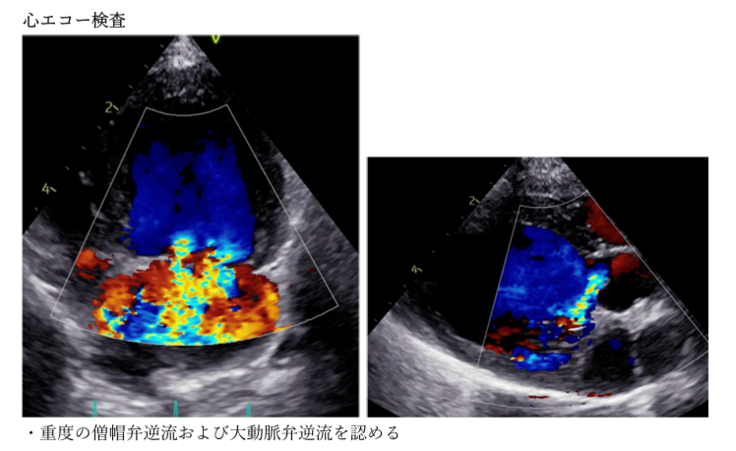

※エコー画像・診断データ・通院記録は信頼性のためページ下資料欄に掲載しております。

【資料欄】(個人情報保護のため、一部モザイク処理させていただいております)

・病院から頂いた所見データ(2025.4.16)